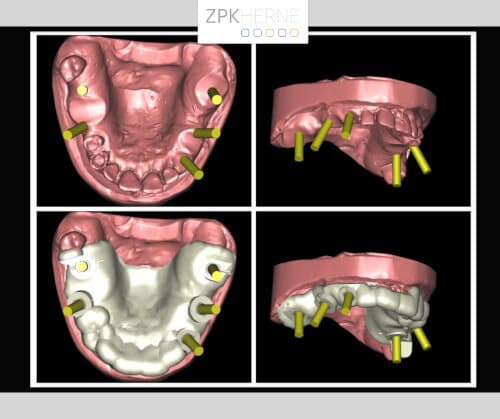

Nach der gründlichen Anamnese werden aktuelle 3D-Aufnahmen der Gebisssituation erstellt. Dabei kommt das Team um Herrn Dr. Mintert zu den folgenden Ergebnissen und Handlungsschritten:

Zur Vorbereitung auf den Tag der Operation wird eine Bohrschablone auf Basis der DVT-Planung angefertigt. So werden die genauen Positionen der einzelnen OP-Schritte festgehalten, damit keine Nervverletzung entsteht. Der chirurgische Eingriff findet unter Vollnarkose statt, hier ist genaueste Konzentration gefragt. Zunächst wird das OP-Gebiet gründlich gereinigt, damit keine Bakterien in die Wunde gelangen. Nun Schnittführung auf den Kieferkämmen: Das Gewebe wird vorsichtig abgelöst und der Knochen freigelegt. Die Bohrschablone wird anprobiert und die Bohrungen für die Implantate Schritt für Schritt durchgeführt. Die Implantate werden nach und nach maschinell eingebracht und radiologisch kontrolliert. Währenddessen wird eine mit Blutplättchen und Wachstumsfaktoren angereicherte Fibrinmembran (LPRF) hergestellt, indem eine gewisse Menge Blut des Patienten zentrifugiert wird. Dies dient der besseren Wundheilung und ist unter dem Begriff „Eigenbluttherapie“ als besonders schonende und effiziente Behandlungsmethode bekannt.